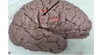

1. Identify the highlighted (red) area. 2. What structure is the black arrow pointing to? 3. What structure is the blue arrow pointing to? 4. What structure is the green arrow pointing to?

1. Occipitotemporal Sulcus 2. Parahippocampal Gyrus/ uncus 3. Medial Occipitotemporal gyrus 4. Lateral Occipitotemporal gyrus